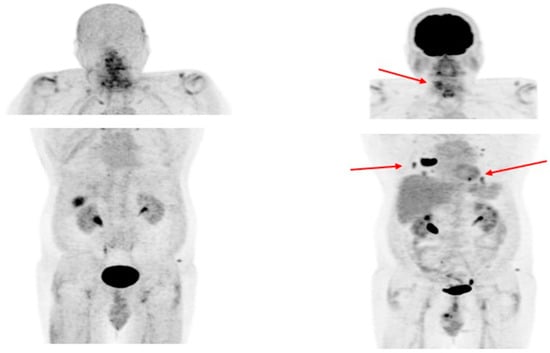

- De Vries, L.H.; Lodewijk, L.; Braat, A.J.A.T.; Krijger, G.C.; Valk, G.D.; Lam, M.G.E.H.; Borel Rinkes, I.H.M.; Vriens, M.R.; de Keizer, B. 68Ga-PSMA PET/CT in Radioactive Iodine-Refractory Differentiated Thyroid Cancer and First Treatment Results with 177Lu-PSMA-617. EJNMMI Res. 2020, 10, 18. [Google Scholar] [CrossRef] [PubMed]

- Rizzo, A.; Racca, M.; Dall’Armellina, S.; Delgado Bolton, R.C.; Albano, D.; Dondi, F.; Bertagna, F.; Annunziata, S.; Treglia, G. Potential Role of PSMA-Targeted PET in Thyroid Malignant Disease: A Systematic Review. Diagnostics 2023, 13, 564. [Google Scholar] [CrossRef]